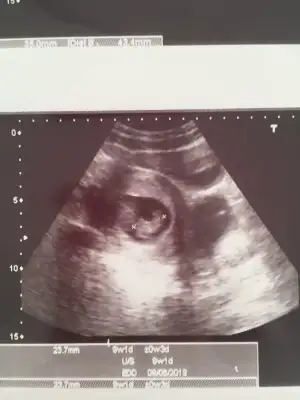

Kızlarr biz de doktordan çıktık minnoşum 9+1 olmuş ve kalbini de duydukdünyanın en tatlı sesiydi galiba

Bulantılarım için folik asidimi değiştirdi ve zencefil önerdi iyi geliyormuş

Hepimize teşekkür ederim kızlar 8 hafta sanıyorken 9 çıkmasına çok sevindim :)

Folidoce kullanıyordum premasis plus şimdi verdiğinin adı. Bebek çok minnoştu baya şekillenmiş ama hatta size ultrasonunu ekleyeyim

Folik asidi de ekliyorum :) zencefili kaynar suya 1 dilim atıp suyu içebilirmişiz. Toz olanıda yoğurtla yiyebilirsin dedi

Canım gözün aydın senin geç döllenmeydi demi? Şimdi haftasını yakaladı mı?Hepimize teşekkür ederim kızlar 8 hafta sanıyorken 9 çıkmasına çok sevindim :)

Folidoce kullanıyordum premasis plus şimdi verdiğinin adı. Bebek çok minnoştu baya şekillenmiş ama hatta size ultrasonunu ekleyeyim

Folik asidi de ekliyorum :) zencefili kaynar suya 1 dilim atıp suyu içebilirmişiz. Toz olanıda yoğurtla yiyebilirsin dedi